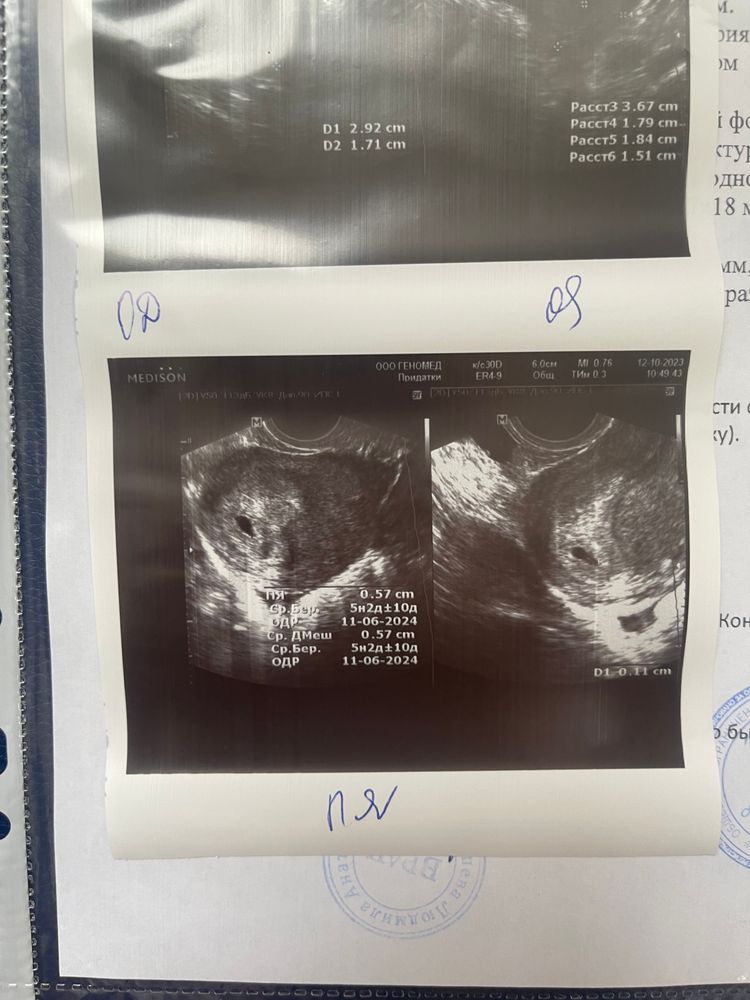

АнализыНу вот и дождались! Были на 1 узи, все хорошо, беременность подтвердили, маточная. Плодное яйцо 5.7

жм 1.1